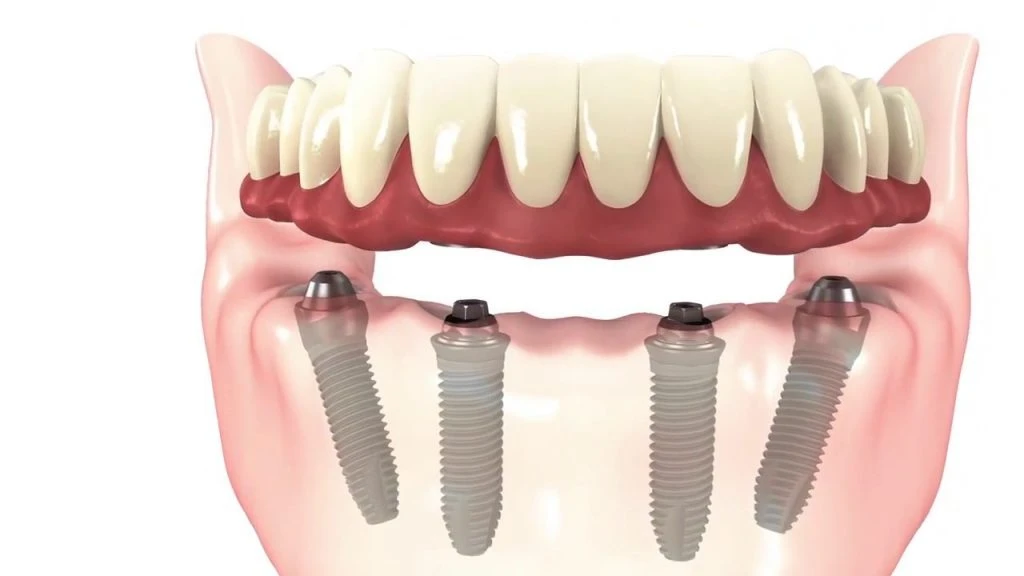

All-on-4 implant tedavisi, tüm dişlerinizi tek seans içerisinde çıkartılıp yerine 4 adet implant üzerine sabitlenen bir köprü ile değiştirmektir. Bu tedavi yöntemi, diş eksiklikleri olan kişilere daha hızlı ve daha kolay bir diş restorasyonu sağlar.

All-on-4 implant tedavisi, bir cerrahi işlemle yapılır. Tedavi sırasında, öncelikle diş etleri kaldırılır ve dişler çekilir. Sonrasında, implantlar çene kemiğine yerleştirilir ve geçici bir köprü takılır. Yerleştirilen implantlar iyileşme sürecinde kemikle kaynaşır ve kalıcı köprü yerleştirilir.

All-on-4 implant tedavisi, hastanın durumuna bağlı olarak değişebilir. İmplantların yerleştirilmesi birkaç saat sürebilirken iyileşme süreci 3-6 ay arasında değişebilir. Tedavi süreci tamamlanana kadar geçici bir köprü takılır.